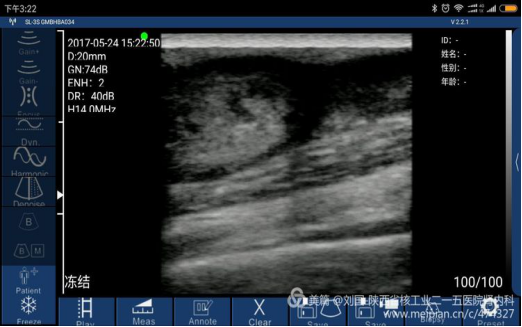

Cephalic vein condition checked by Sonostar’s wireless ultrasound, and displayed by my mobile phone-Mi max

Cut tumor